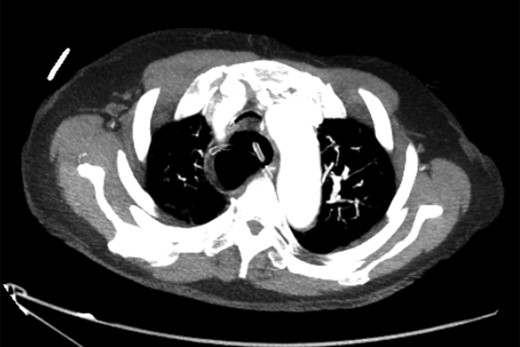

Axial slice of CT chest after nasogastric decompression showing persistent megaoesophagus and airway narrowing.